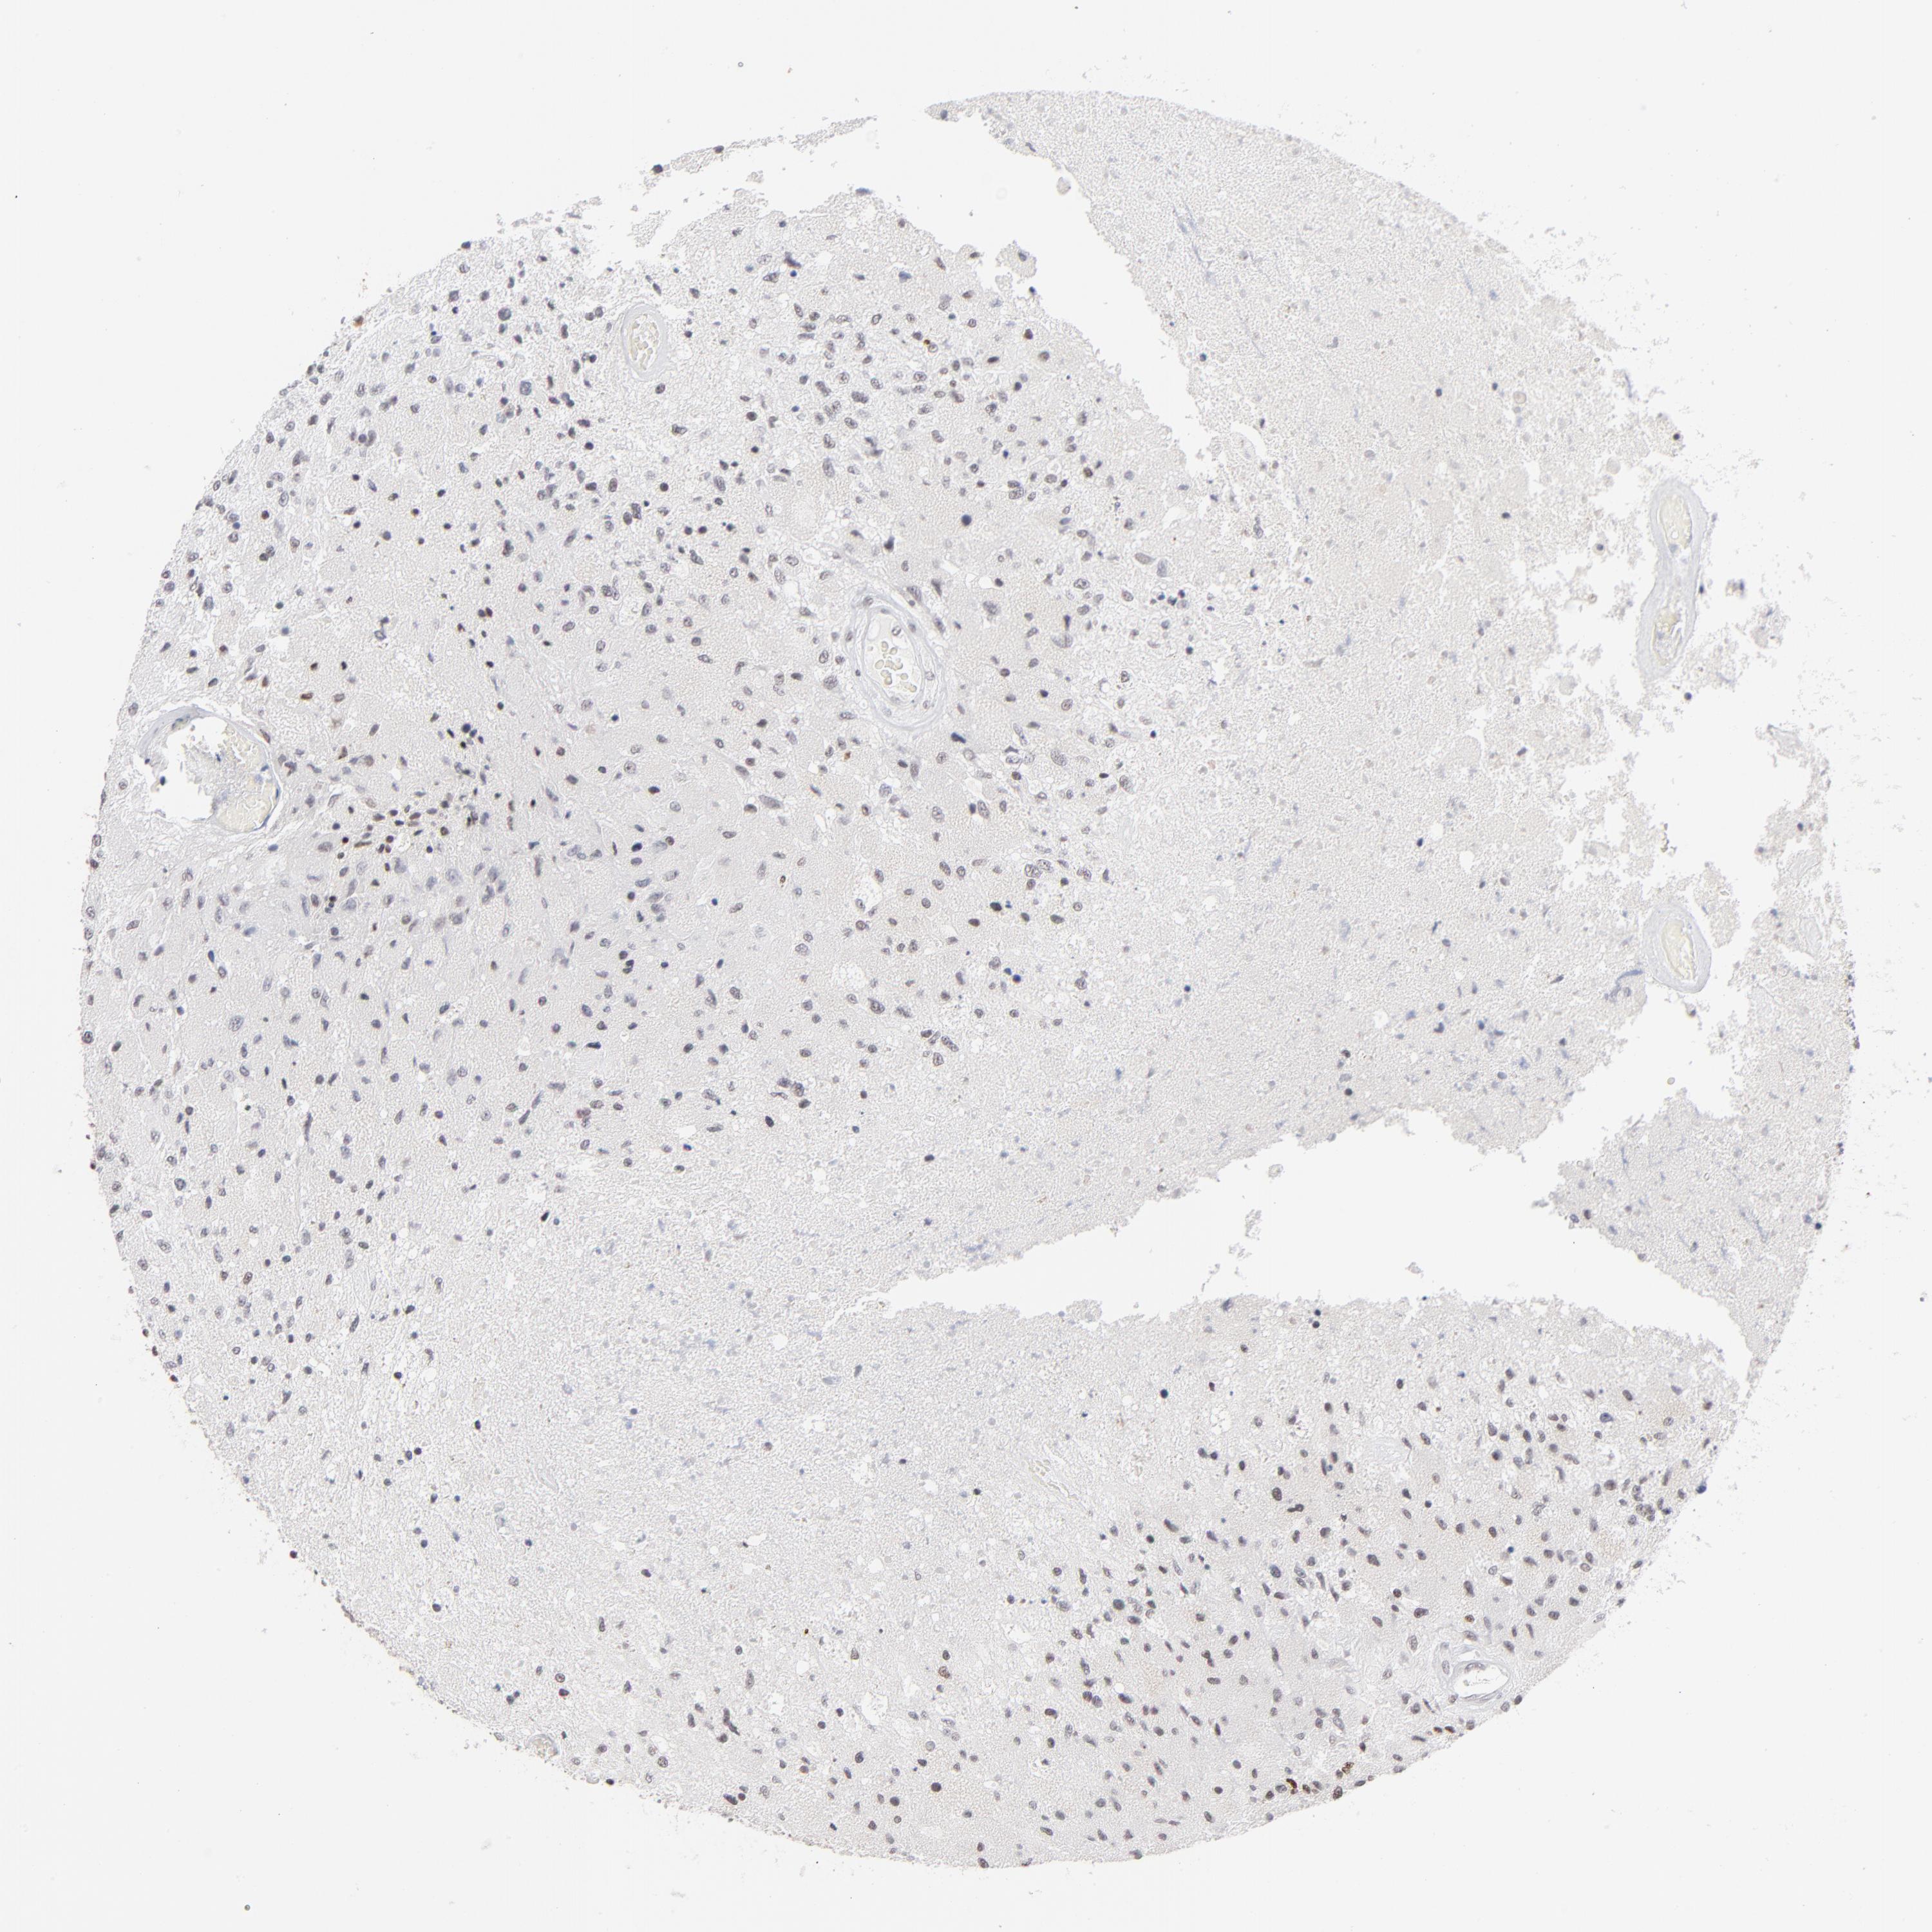

GLIOMA - Protein expressioni

A mouse-over function shows sample information and annotation data. Click on an image to view it in a full screen mode. Samples can be filtered based on level of antibody staining by selecting one or several of the following categories: high, medium, low and not detected. The assay and annotation is described here.

Note that samples used for immunohistochemistry by the Human Protein Atlas do not correspond to samples in the TCGA dataset.

Antibody stainingi

Antibody staining in the annotated cell types in the current human tissue is reported as not detected, low, medium, or high, based on conventional immunohistochemistry profiling in selected tissues. This score is based on the combination of the staining intensity and fraction of stained cells.

Each image is clickable and will lead to virtual microscopy that enables deeper exploration of all samples and also displays staining intensity scores, fraction scores and subcellular localization as well as patient and tissue information for each sample.

Antibody HPA003263

Staining

High

Medium

Low

Not detected

Intensity

Strong

Moderate

Weak

Negative

Quantity

>75%

75%-25%

<25%

None

Location

Nuclear

Cytoplasmic/membranous

Cytoplasmic/membranous,nuclear

Glioma, malignant, High grade

Glioma, malignant, NOS

Glioma, malignant, Low grade